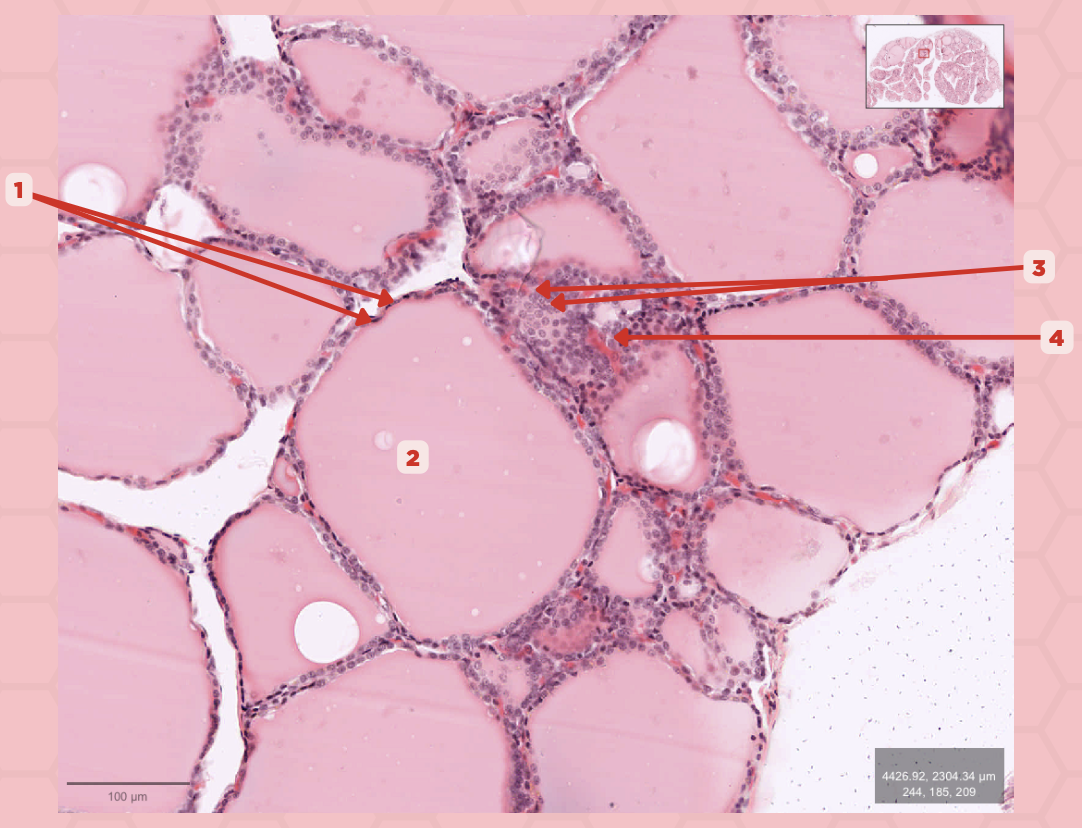

T3 and T4 Hormone

What type of hormone is being secreted by the pointer #1?

Follicular Cells

Identify the structure labeled as 1.

Colloid

Identify the structure labeled as 2.

Parafollicular Cells

Identify the structure labeled as 3.

Capillary

Identify the structure labeled as 4.